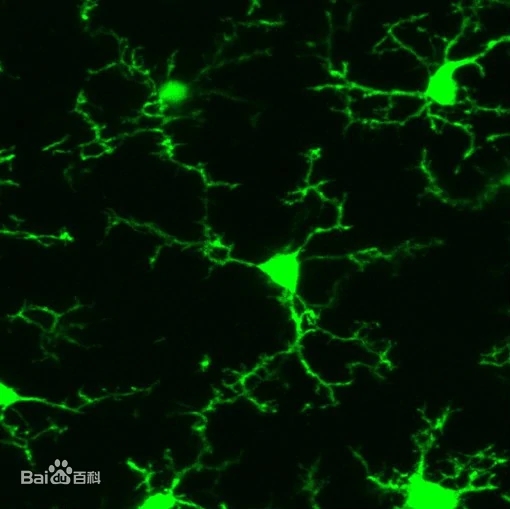

學(xué)習資源根據(jù)荷蘭神經(jīng)科學(xué)研究所的一項研究,抑郁癥與大腦中被抑制的小膠質(zhì)細胞有關(guān)。該研究表明,神經(jīng)元與小膠質(zhì)細胞的相互作用受到干擾,為潛在的新治療干預(yù)打開了大門。